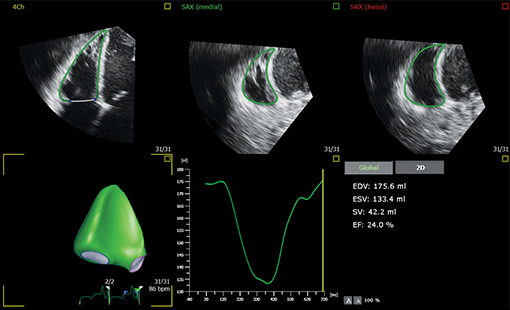

Evolving from Philips HeartModel, Dynamic HeartModel provides more critical capabilities in addition to LV and LA volumes to expand your clinical use and increase diagnostic confidence through 3D echocardiography technology. The Dynamic HeartModel tracks every frame over the cardiac cycle using 3D speckle technology. The moving contours of LA and LV borders and waveforms, additional LV, LA indexes and LV mass measurements provide a holistic view of the left heart function. The LV wall motion and the linkage between the LV and LA volume change over the heart cycle in order to increase your diagnostic confidence. In addition, the multi-beat selection and results average make the heart function evaluation more reliable than single beat, being ideal for arrhythmia or atrial fibrillation patients.

Boost your confidence in cardiac quantification during everyday workflows with HeartModel. This intuitive and validated 3D tool provides robust, reproducible ejection fraction (EF) in just seconds. What’s more, HeartModel is the only validated tool to provide simultaneous LV and LA volumes. It helps you easily characterize LA volume – shown to be an indicator of cardiovascular outcomes – to yield additional clinical information with no extra time or steps.

This study compared quantification between 2D and Live 3D HeartModel and demonstrated a 82% time savings for HeartModel when using the automated capability, and 63% time savings when minor edits were required.